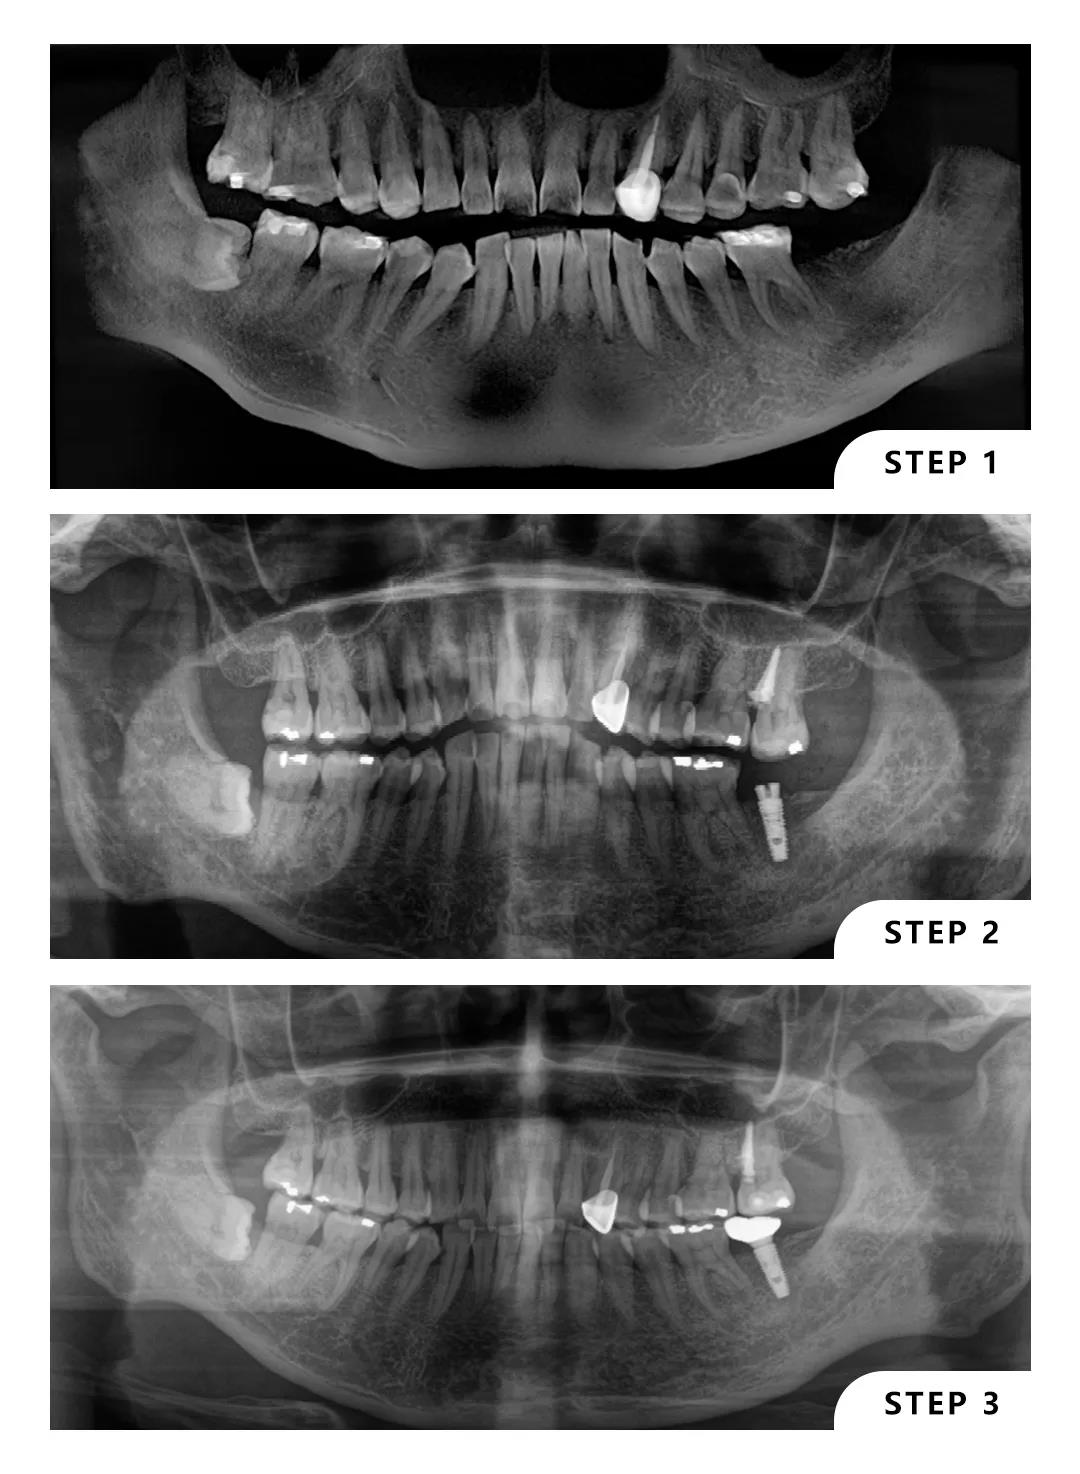

这位患者左下7缺失,左上7伸长,患者本人可以接受种植,但不接受磨牙。

曹医生在面诊后给出了左上7向上牵引,左下7种植的方案,经过一年的努力,患者对效果很满意。

从正畸到种植,曹医生擅长通过综合的方案运用微创种植能够以最小的创伤最快的速度给患者解决问题。